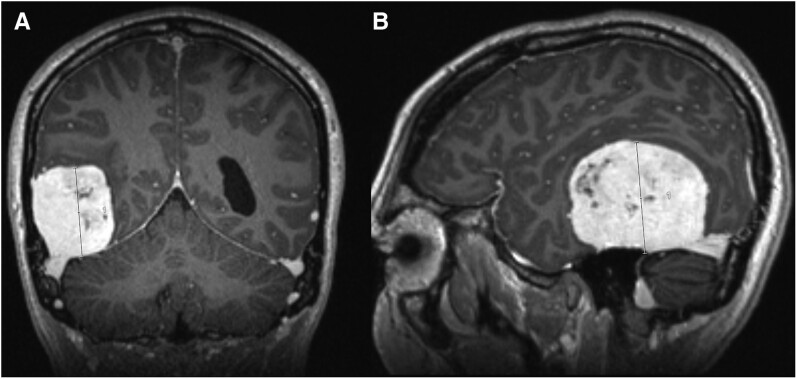

孕激素相关脑膜瘤是醋酸环丙孕酮(CPA)的一种罕见并发症,醋酸环丙孕酮是一种抗雄激素,通常用于变性人和性别多样化者的女性化激素治疗方案。据观察,这种疾病与剂量反应有关,尤其是长期暴露于每天≥50 毫克的剂量时;然而,低于多少剂量使用 CPA 才是安全的,目前仍不清楚。我们在此报告了两名使用 CPA 的变性女性患脑膜瘤的病例。这些病例的新颖之处包括(i) 一名患者出现无症状的巨大脑膜瘤(> 5 厘米),包括需要紧急手术干预的多发性脑膜瘤;(ii) 使用高剂量、长疗程和低剂量、短疗程 CPA 均出现脑膜瘤;(iii) 一名患者出现 PIK3CA 错义变异,这可能在孕激素相关脑膜瘤的发病机制中发挥作用。我们的病例凸显了这种可能未得到充分报道的不良反应在现实世界中的风险,并强调了临床医生警惕神经系统后遗症的重要性。我们建议使用能维持充分雄激素抑制的最低剂量 CPA,并酌情考虑使用其他抗雄激素。

Progestin-associated meningioma is a rare complication of cyproterone acetate (CPA), an anti-androgen commonly prescribed in feminizing hormone therapy regimens for transgender and gender-diverse individuals. A dose-response association has been observed, particularly with longer-term exposure to doses ≥ 50 mg daily; however, the dose below which CPA use is safe remains unclear. We herein report the cases of 2 transgender women using CPA who developed meningioma. Novel aspects of our cases include: (i) the presence of symptomatic giant meningiomas (> 5 cm), including multiple meningiomas in one patient, requiring urgent surgical intervention; (ii) meningioma development with both high-dose, long duration and low-dose, shorter duration CPA; and (iii) the presence of a PIK3CA missense variant in one patient, which may play a role in the pathogenesis of progestin-associated meningioma. Our cases highlight the real-world risk of this likely underreported adverse effect and underscore the importance of clinician vigilance for neurological sequelae. We suggest using the lowest dose of CPA that maintains adequate androgen suppression, with consideration of alternative anti-androgens where appropriate.